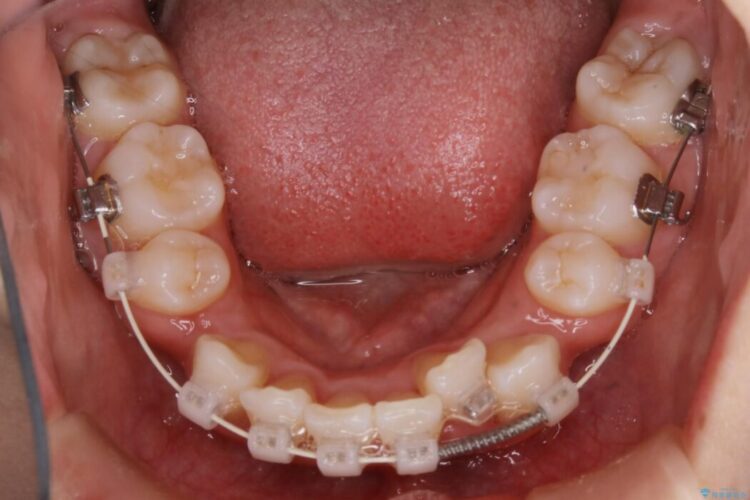

- 矯正装置:ワイヤー(審美装置)

検査したところ歯に対して骨が上顎・下顎共に小さいことがわかりました。

それによりスペースが少なく歯列がガタついたり前方傾斜する生え方となっていました。

よって本症例では抜歯により歯の本数を減らすことにより整えるスペースを確保してワイヤー装置にて歯列矯正を行うこととしました。

本症例の患者様は顎の骨が小さく歯をきれいに並べるための隙間がないため、歯が重なったり傾斜してしまっていました。

抜歯を行うことによりスペースを確保し、小さい骨幅でも歯並びを整えることができます。